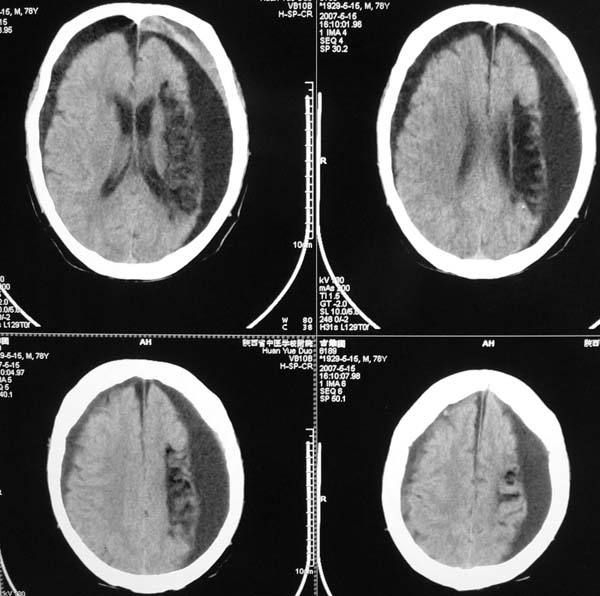

以下是引用star--868在2007-6-15 20:54:00的发言:[br]1.左侧额颞顶部亚急性硬膜下血肿并继续出血 双侧额颞顶部硬膜下积液;[br]2.左颞枕叶、左基底节区脑软化-左侧大脑中动脉栓塞;[br]双侧额颞顶部硬膜下积液应和治疗期间应用高渗脱水剂相鉴别:停用甘露醇后硬膜下积液会逐渐吸收减少,而单纯硬膜下积液无此改变和/或逐渐增多。

以下是引用狙击手在2007-6-15 21:15:00的发言:[br]软化灶就不必说了,主要是混和性血肿的渐变过程。

以下是引用老爱克斯新网客在2007-6-15 20:40:00的发言:[br]1左侧颞叶软化灶,2双侧硬膜下水瘤,3左册硬膜下血肿(多次少量出血),

以下是引用还珠格格在2007-6-16 7:07:00的发言:[br]支持.左侧额颞顶部亚急性硬膜下血肿并继续出血 双侧额颞顶部硬膜下积液;[br]2.左颞枕叶、左基底节区脑软化-左侧大脑中动脉栓塞;